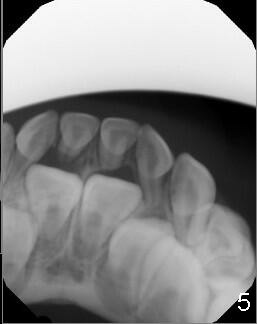

When Devon is 5 years old, there are no spaces between the deciduous teeth (Fig.4-6). The developing upper central incisors are deviated from the midline and off angle (Fig.4: black lines, as compared to Fig.1). Two upper deciduous lateral incisors are in cross bite (Fig.6). LR6 (lower right permanent first molar) rotates (Fig.7 *, as compared to normal LL6 in Fig.8).

当Devon五岁时,没有乳牙间隙(图四至图六),正在发育的恒中切牙不仅远离中线,而且角度不对(图四:斜线,与图一:8,9(恒中切牙)比较)。乳侧切牙反合(图六:D, G)。右下第一恒磨牙扭转(图七:*,与图八:左下相应牙齿对比)。